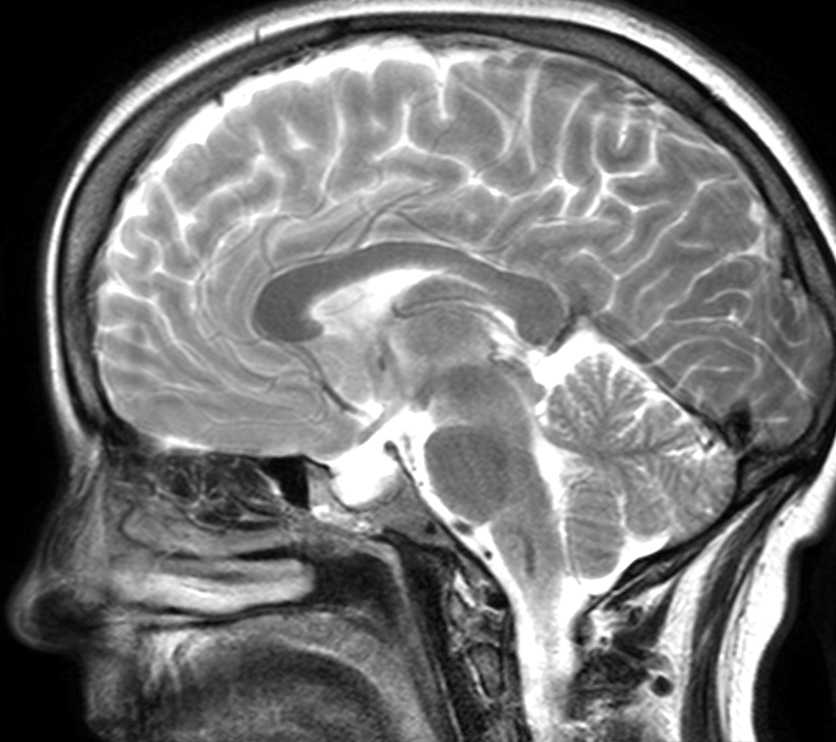

I have an MRI scan of my brain because some doctors wanted a closer look at it. Either I am a raving lunatic, or because I have a remarkable brain. One – or both.

- saggital

The point though, is that this is done in three axes: axial, saggital, coronal. So you can generate a 3D model that have three axes to average from, instead of one – meaning that the 3D model will not look like it was built from lego. As it would, if it only was one axis. I swear, i will 3D-print my brain when I get my head around the software.

The original has about 30 saggital slices, which are too many: so i picked 13 of them, aligned them in layers in Illustrator, and drew roughly the brain structure of each slice. I calculated from the center – the slice where my nose are pretty much cut in two and added six slices before and after.